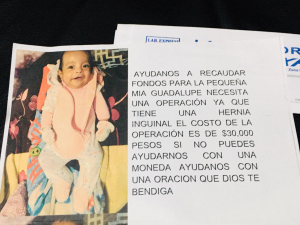

Familia de una bebé matamorense está pidiendo la ayuda económica de la comunidad para así solventar los gastos de una operación que cuesta más de 30 mil pesos.

Mia Guadalupe, de tan sólo 3 meses de edad enfrenta este padecimiento después de su nacimiento, tiene una hernia inguinal de lado  izquierdo.

La madre de la bebé, Selena está preparando una colecta en esta ciudad fronteriza para pagar la cantidad que se pide para esta operación.

A las personas que gusten ayudar a esta causa pueden comunicarse celular de contacto 8682207600 o bien se pueden comunicar por mensaje al Whats App 8681062447.

Si gusta hacer alguna transferencia a bancaria puede hacer su donativo al número de tarjeta Saldazo Banamex 4766 8415 5227 7991.